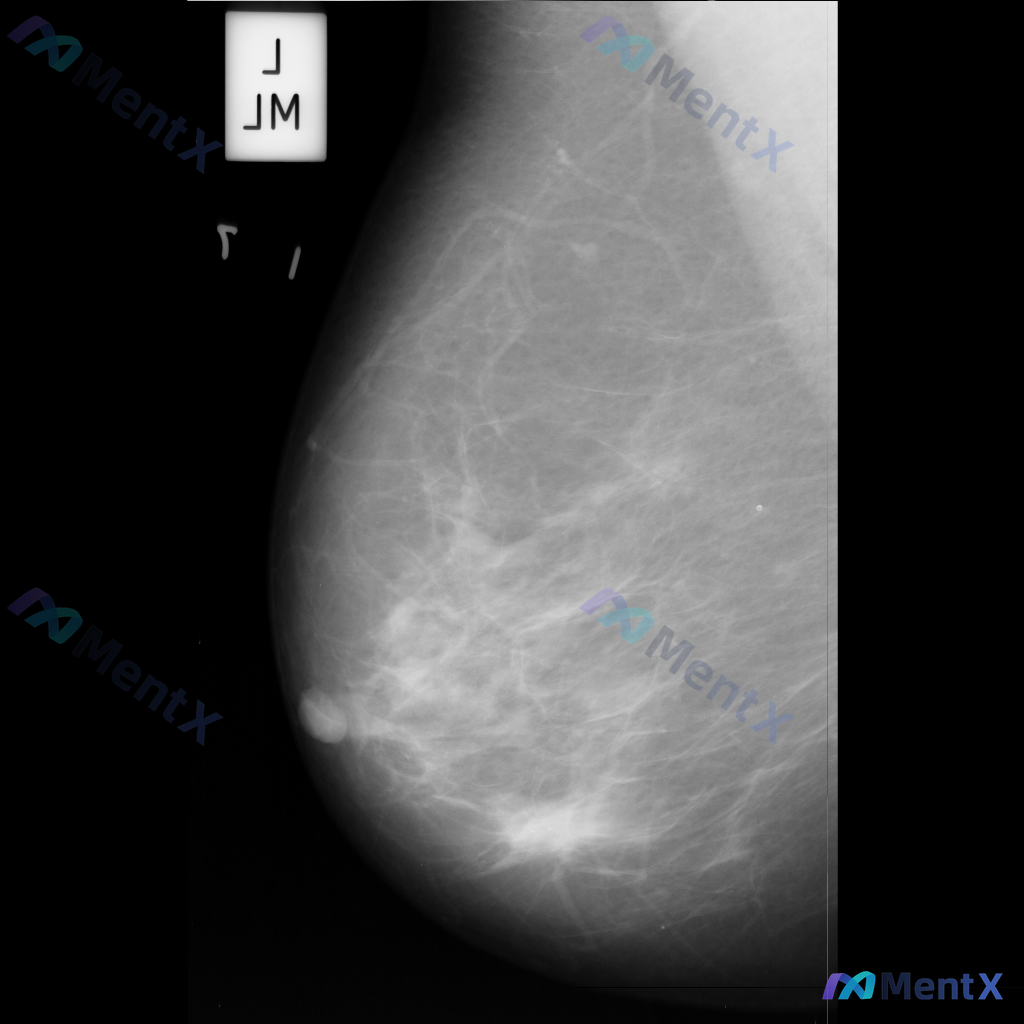

各位同道好,今天分享一则左乳钼靶病例,影像表现如下: 1. 左乳下方(近乳头区)可见一个边界清晰、形态卵圆形的等/稍高密度肿块影; 2. 左乳中央及下象限腺体局部密度增高和结构紊乱; 3. 散在分布的粗大点状钙化。 上传的钼靶影像编号为mdb083.png,供大家参考。 针对这组表现,你更倾向于哪种...